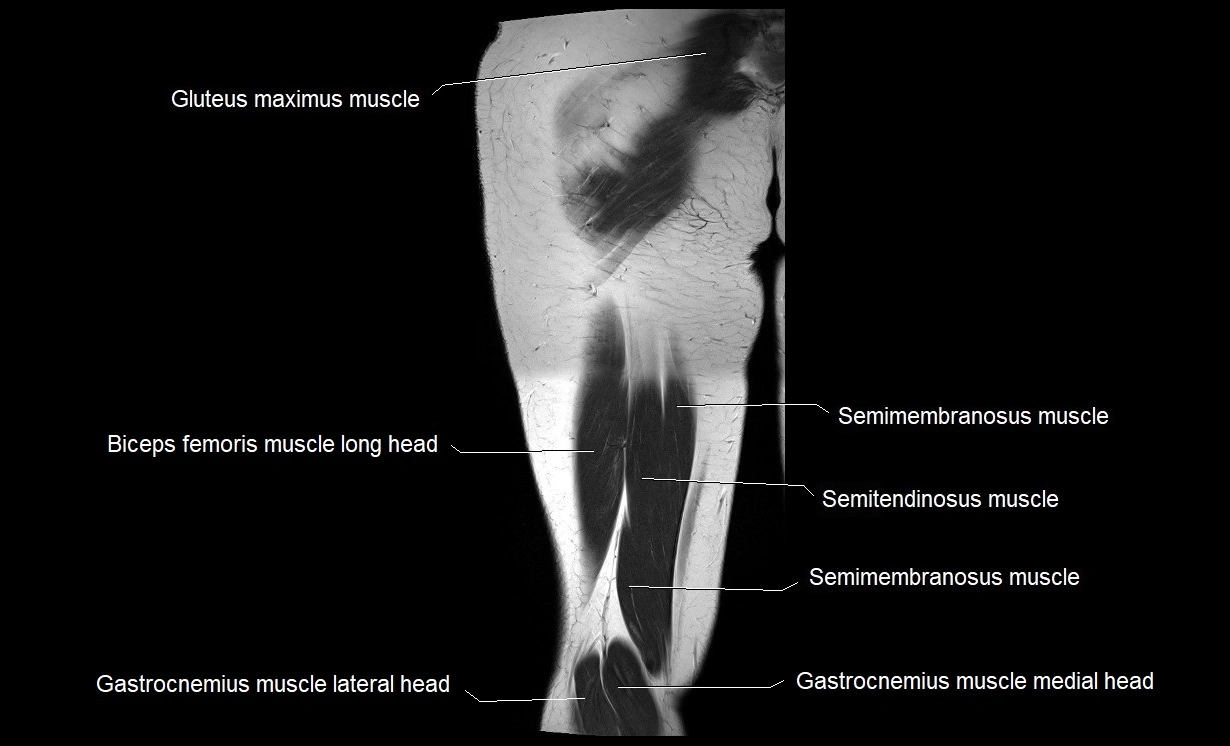

- Biceps femoris muscle (Long head)

- Gastrocnemius muscle

- Gluteus maximus muscle

- Medial head of gastrocnemius muscle

- Semimembranosus muscle

- Semitendinosus muscle